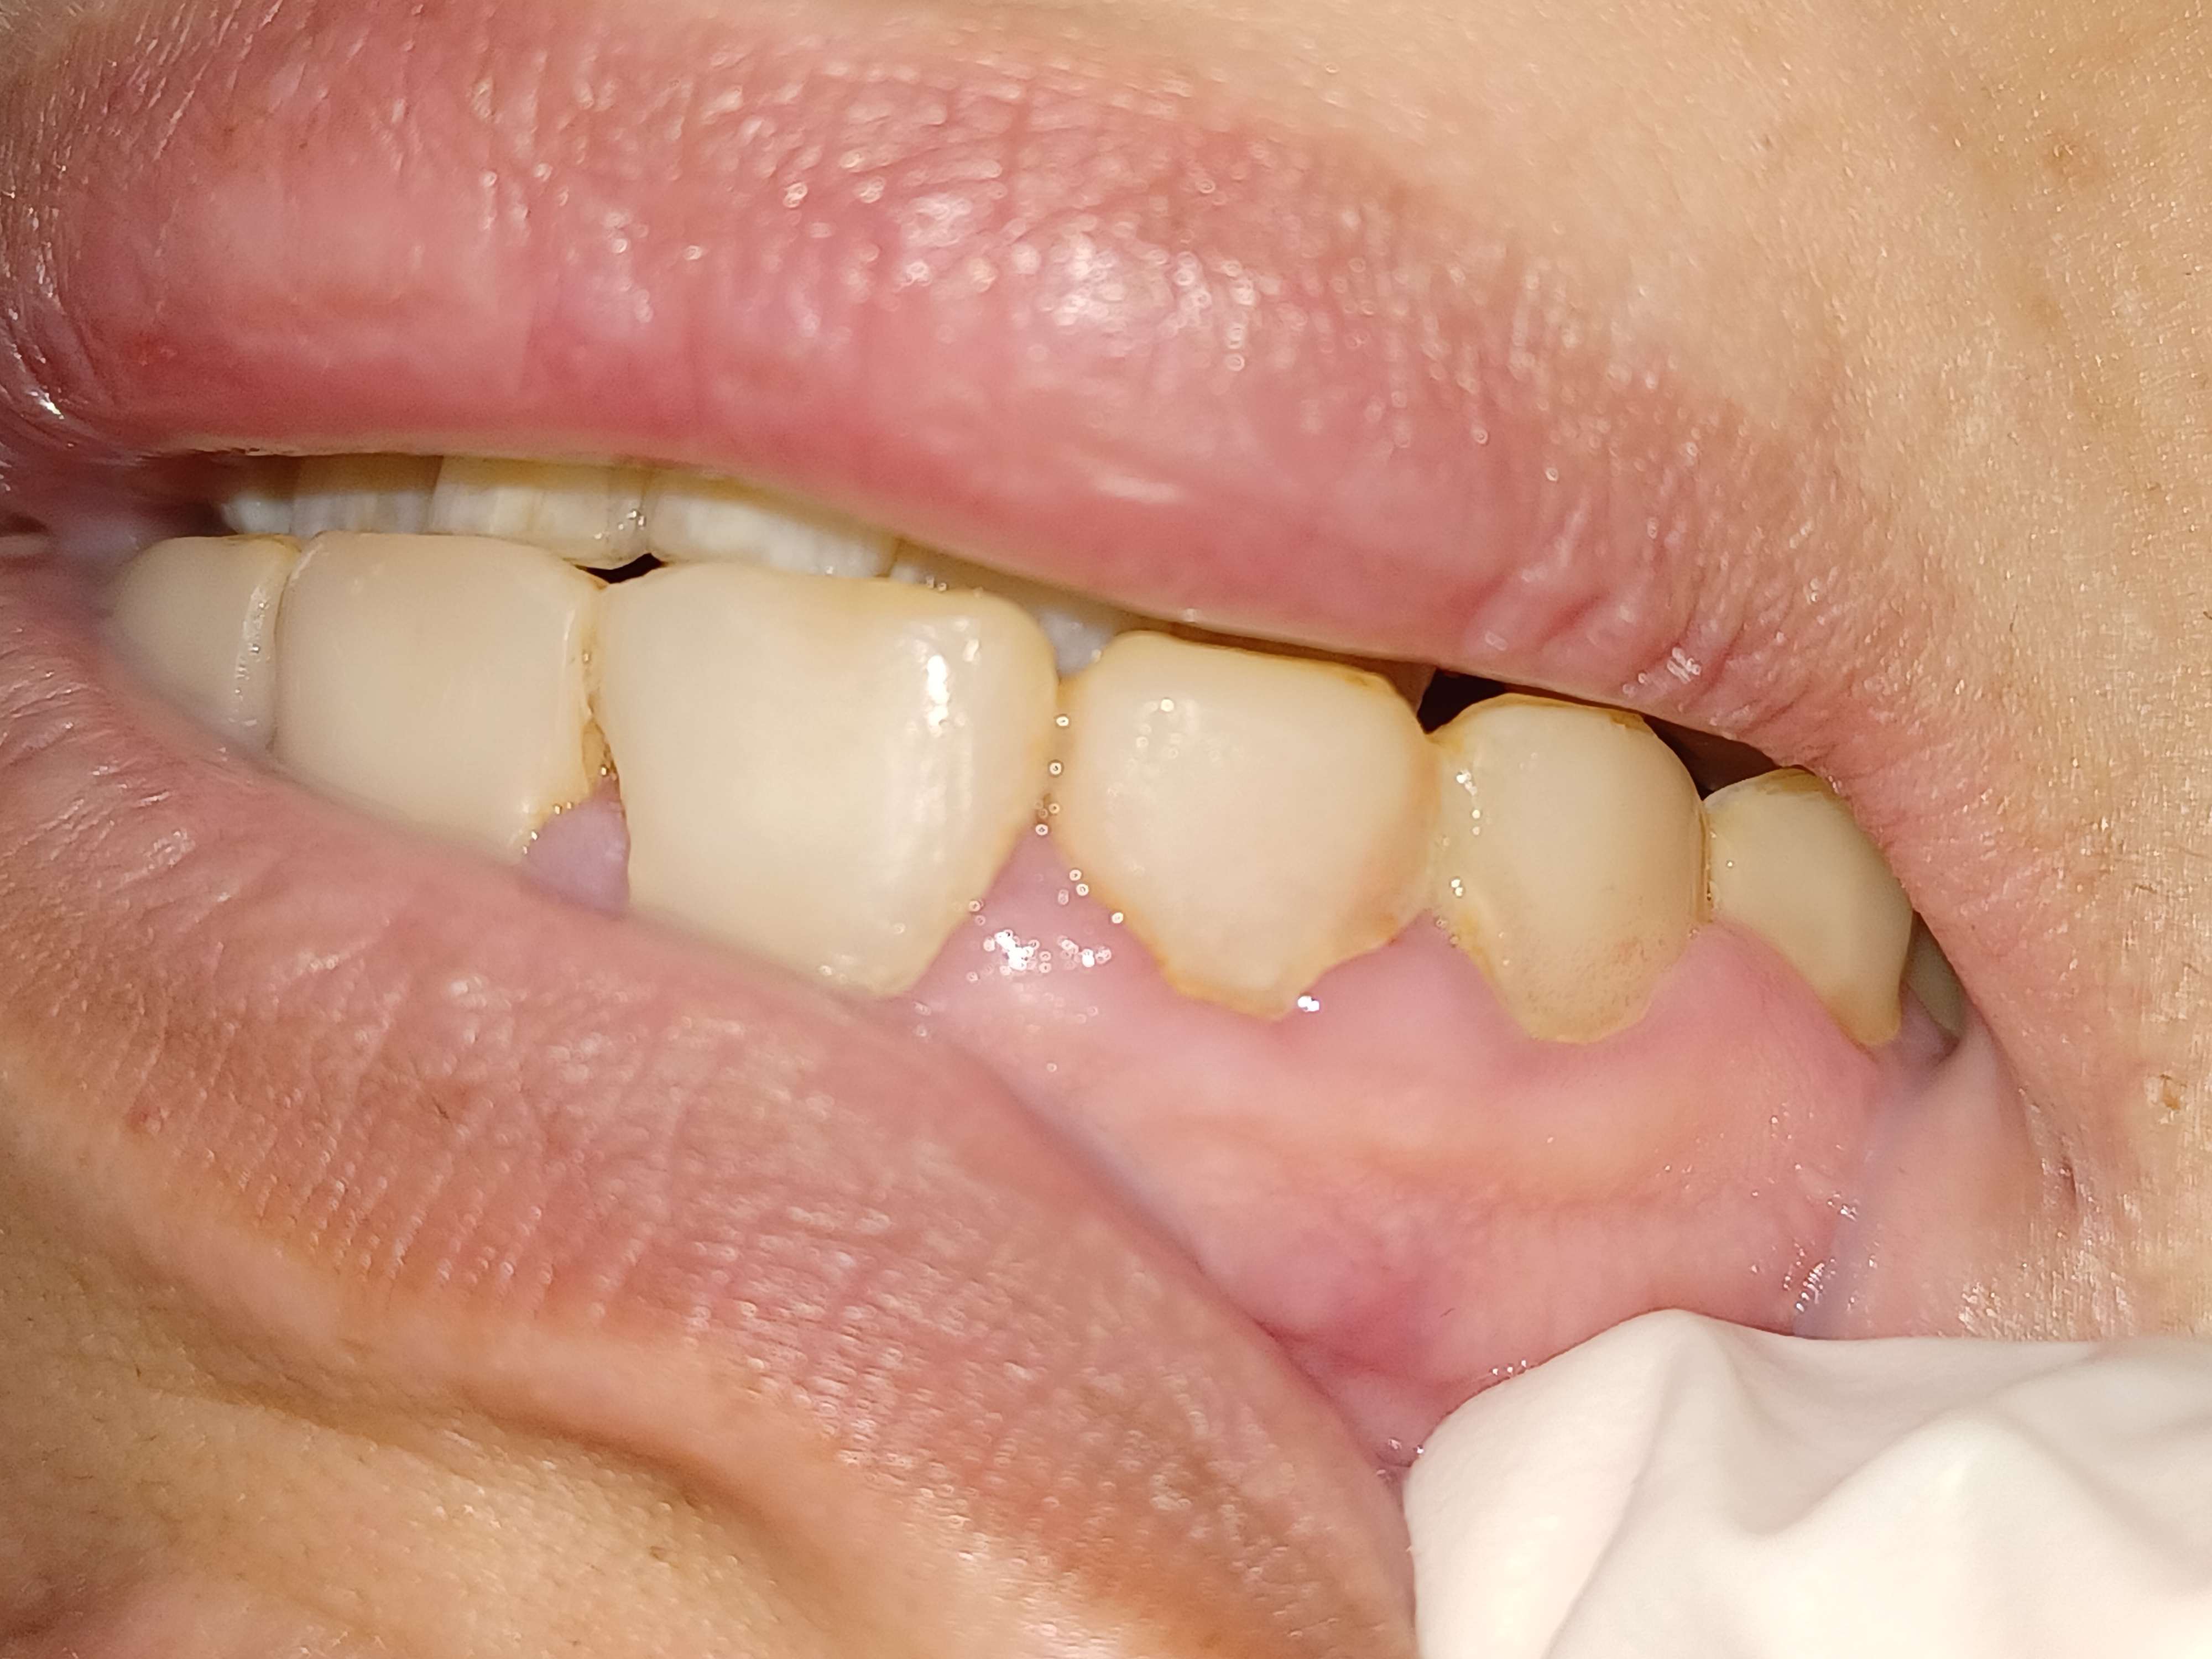

Y’a pas de doutes c’est clairement des compos.

Clairement le style de patient qu’il faut driver dès le début.

Assister à mort sur la nécessité de déposer minutieusement le truc, le « veneer », ou le fromage fondu qu’elle a sur les dents et sur la mise en condition gingivale AVANT de proposer quoique ce soit.

Par contre que les compos aient été réalisés à la 6 4 2 , cela ne fait guère de doute.

Oui enfin, y'a pas un espace interdentaire sans inflammation, en haut comme en bas, même là ou les compos ne sont pas juxta sulcus. Toutes les papilles sont inflammatoires. Donc c'est sûr que faire des facettes, en plus à l'arrache sur ce genre de cas ça ne peut pas donner un joli résultat.

C'est marrant, moi je pense à l'inverse qu'on ne pourra pas régler le problème paro tant qu'on n'aura pas réglé le problème des "facettes" iatrogènes, au moins au Mx.

Franchement, elle a peut être bien brossé avant le RDV mais il n'y a quasiment pas de plaque, et l'inflammation est limitée. Pour moi c'est 90% iatrogène, améliorer l'hygiène n'y changera pas grand chose.

A minima un petit coup de fraise grain fin pour éliminer les surcontours, avant de reprendre proprement un plan de traitement complet.

Les dents sont parfois même solidarisées au compo.

Non première étape : éliminer tout les surplombs et stripper tout les points de contact.